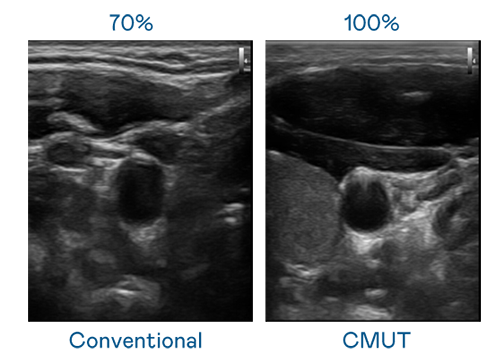

CMUT 技术是一种用电容式微机电元件来产生超音波讯号的技术。与传统 PZT 压电式技术相比,CMUT 频宽增加 3友达%,更宽频的超音波讯号让影像解析度大幅提升,是实现高影像品质医疗超音波扫描、促进精准医疗发展的关键技术。

大频宽带来超清晰影像

超音波影像的解析度高低,首先取决于探头能发出的讯号频宽。友达 CMUT 可提供高清晰的超音波讯号,提供高频宽、高灵敏度、影像纹理细节更高的超音波影像,协助医护人员缩短影像判读时间及利用精准的医疗影像进行诊断。